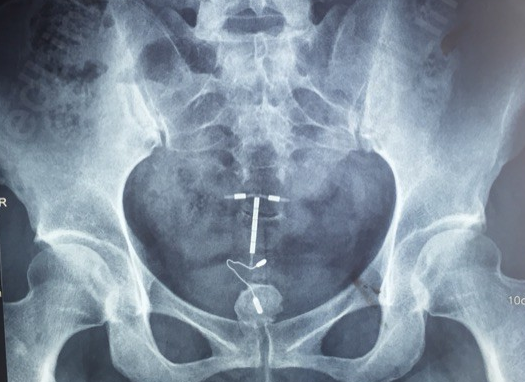

图片

异物(节育环)导致的结石